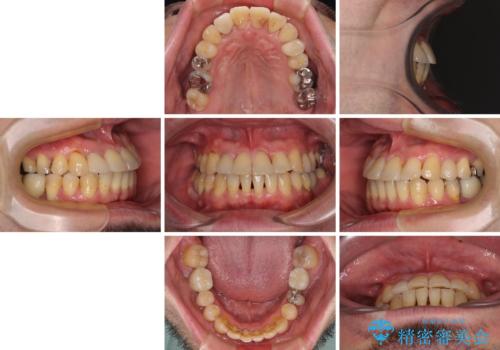

矯正治療でインプラント埋入を行い、矯正治療後に気になる前歯と合わせてオールセラミッククラウンによる補綴治療を行うこととしました。

骨造成や歯肉移植など、治癒期間の長い処置を必要としたため治療期間は長くなりましたが、安定した咬み合わせと整った歯列となり、患者様には大変満足していただきました。